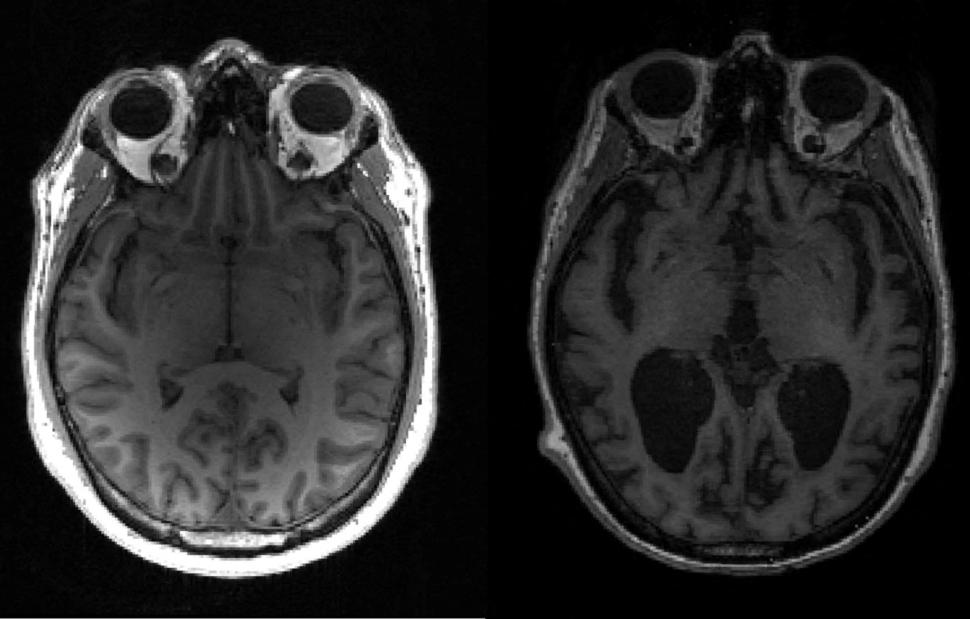

Μέχρι σήμερα, οι πιο αξιόπιστες μέθοδοι για την ανίχνευση της νόσου Αλτσχάιμερ απαιτούσαν επεμβατικές και δαπανηρές τεχνικές, όπως η λήψη εγκεφαλονωτιαίου υγρού. Οι επιστήμονες διερευνούν εδώ και χρόνια τη δυνατότητα εντοπισμού της νόσου, η οποία προσβάλλει 800.000 άτομα μόνο στην Ισπανία, με μια εξέταση αίματος, λόγω των δυνατοτήτων της να βελτιώσει την έγκαιρη διάγνωση.

Σύμφωνα με τον Ελόι Ροντρίγκεζ, επικεφαλής του Τμήματος Νευρολογίας στο Πανεπιστημιακό Νοσοκομείο Marqués de Valdecilla-IDIVAL, η πρόοδος αυτή "θα συμβάλει στον εκδημοκρατισμό της βιολογικής διάγνωσης ακριβείας της νόσου Αλτσχάιμερ", η οποία θα αποφύγει σε πολλές περιπτώσεις πιο επεμβατικές ή δυσπρόσιτες τεχνικές, όπως η οσφυονωτιαία παρακέντηση ή η PET αμυλοειδούς, μια πολύ ακριβή απεικονιστική εξέταση. Ο εμπειρογνώμονας είναι αισιόδοξος για τη δυνατότητα επέκτασης της χρήσης αυτού του δείκτη "από εξειδικευμένες σε λιγότερο εξειδικευμένες επισκέψεις".